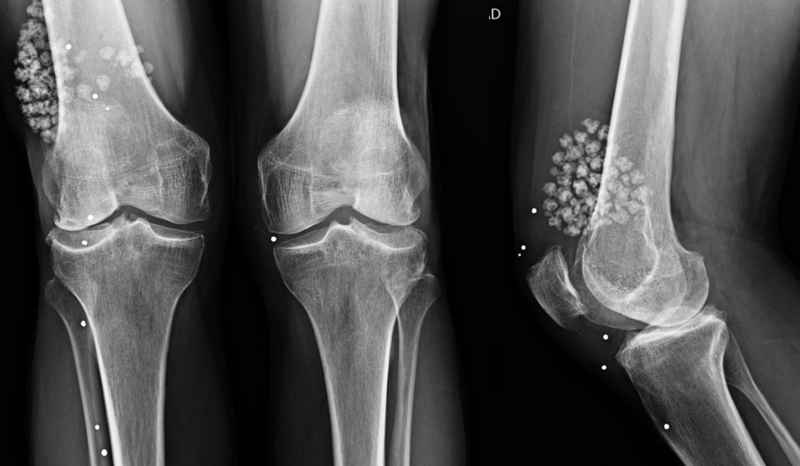

Bệnh lý u sụn màng hoạt dịch là một dạng dị sản lành tính xảy ra ở bao hoạt dịch khớp, khi này các tế bào liên kết có khả năng tự tạo ra sụn. Bên trong ổ khớp, các khối sụn nhỏ xuất hiện chồi lên trên bề mặt của sụn khớp, phát triển thành cuống và hình thành các u sụn màng hoạt dịch. Sau quá trình này, các khối u sẽ xơ cứng lại, được gọi tên là u sụn màng hoạt dịch.

Trong một số trường hợp sụn nhỏ sẽ rơi vào bên trong ổ khớp và hình thành các dị vật khớp, từ đó tạo nên các ảnh hưởng nghiêm trọng đến khả năng vận động của khớp, gây đau nhức mỗi khi hoạt động, giảm vận động, kém linh hoạt khớp, viêm màng dịch và tăng nguy cơ tràn dịch khớp gối.

Chẩn đoán u sụn màng hoạt dịch cận lâm sàng: